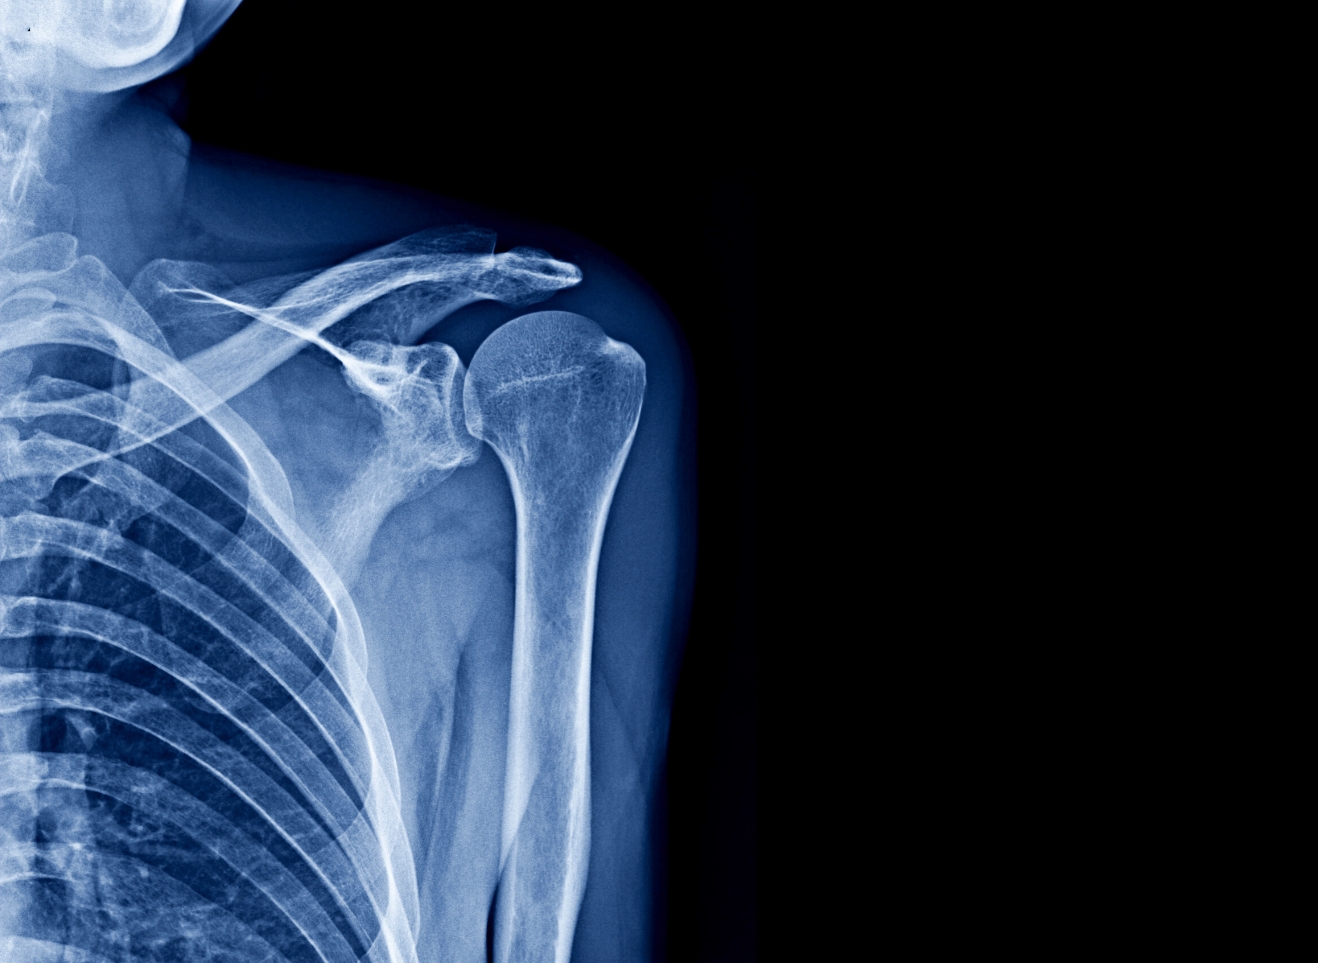

Försvagat ben kan leda till frakturer vid skelettcancer.

Röntgen, datortomografi (DT), magnetresonanstomografi (MRT) och skelettskintigrafi används för att kartlägga tumörens storlek och spridning. Dessa undersökningar kallas gemensamt för bilddiagnostik. Förändringar som syns på röntgen eller MRT kallas ofta tumörer, vilket kan vara både godartade och elakartade vävnadsförändringar. Datortomografi kan ge svar på hur stort ett eventuellt sarkom är och om det har spridit sig.

Magnetkamera används för att undersöka skelettcancer och kan visa tumörens storlek och spridning. Vid misstanke om cancer och skelettmetastaser utförs skelettskintigrafi för att undersöka skelettets aktivitet. Kombinationen av dessa ger en detaljerad bild av sjukdomen.